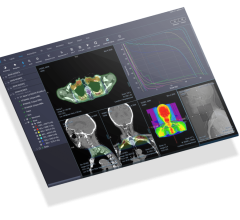

June 4, 2024 — International medical imaging IT and cybersecurity company Sectra has launched a new diagnostic IT module ...